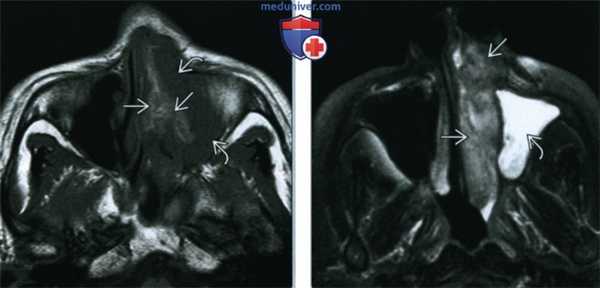

(Слева) При аксиальной МРТ Т1 определяется объемное образование в полости носа слева, распространяющееся в верхнечелюстную пазуху. Опухоль неоднородна и содержит зоны с гиперинтенсивным (Т1) и промежуточным сигналом. Гиперинтенсивный (Т1) сигнал на безконтрастных изображениях может свидетельствовать о наличии меланина или кровоизлияния.

(Справа) При аксиальной МРТ Т1 FS визуализируется меланома Ш в полости носа слева. Опухоль несколько гипоинтенсивна и легко отличима от гиперинтенсивного «запертого» секрета в верхнечелюстной пазухе.